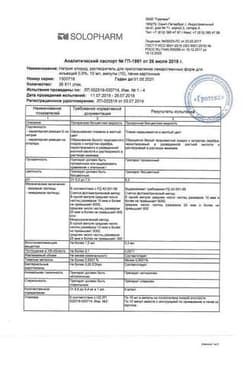

Сертификаты